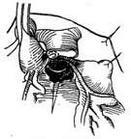

冠状动脉解剖示意图(剥除心包、心耳)